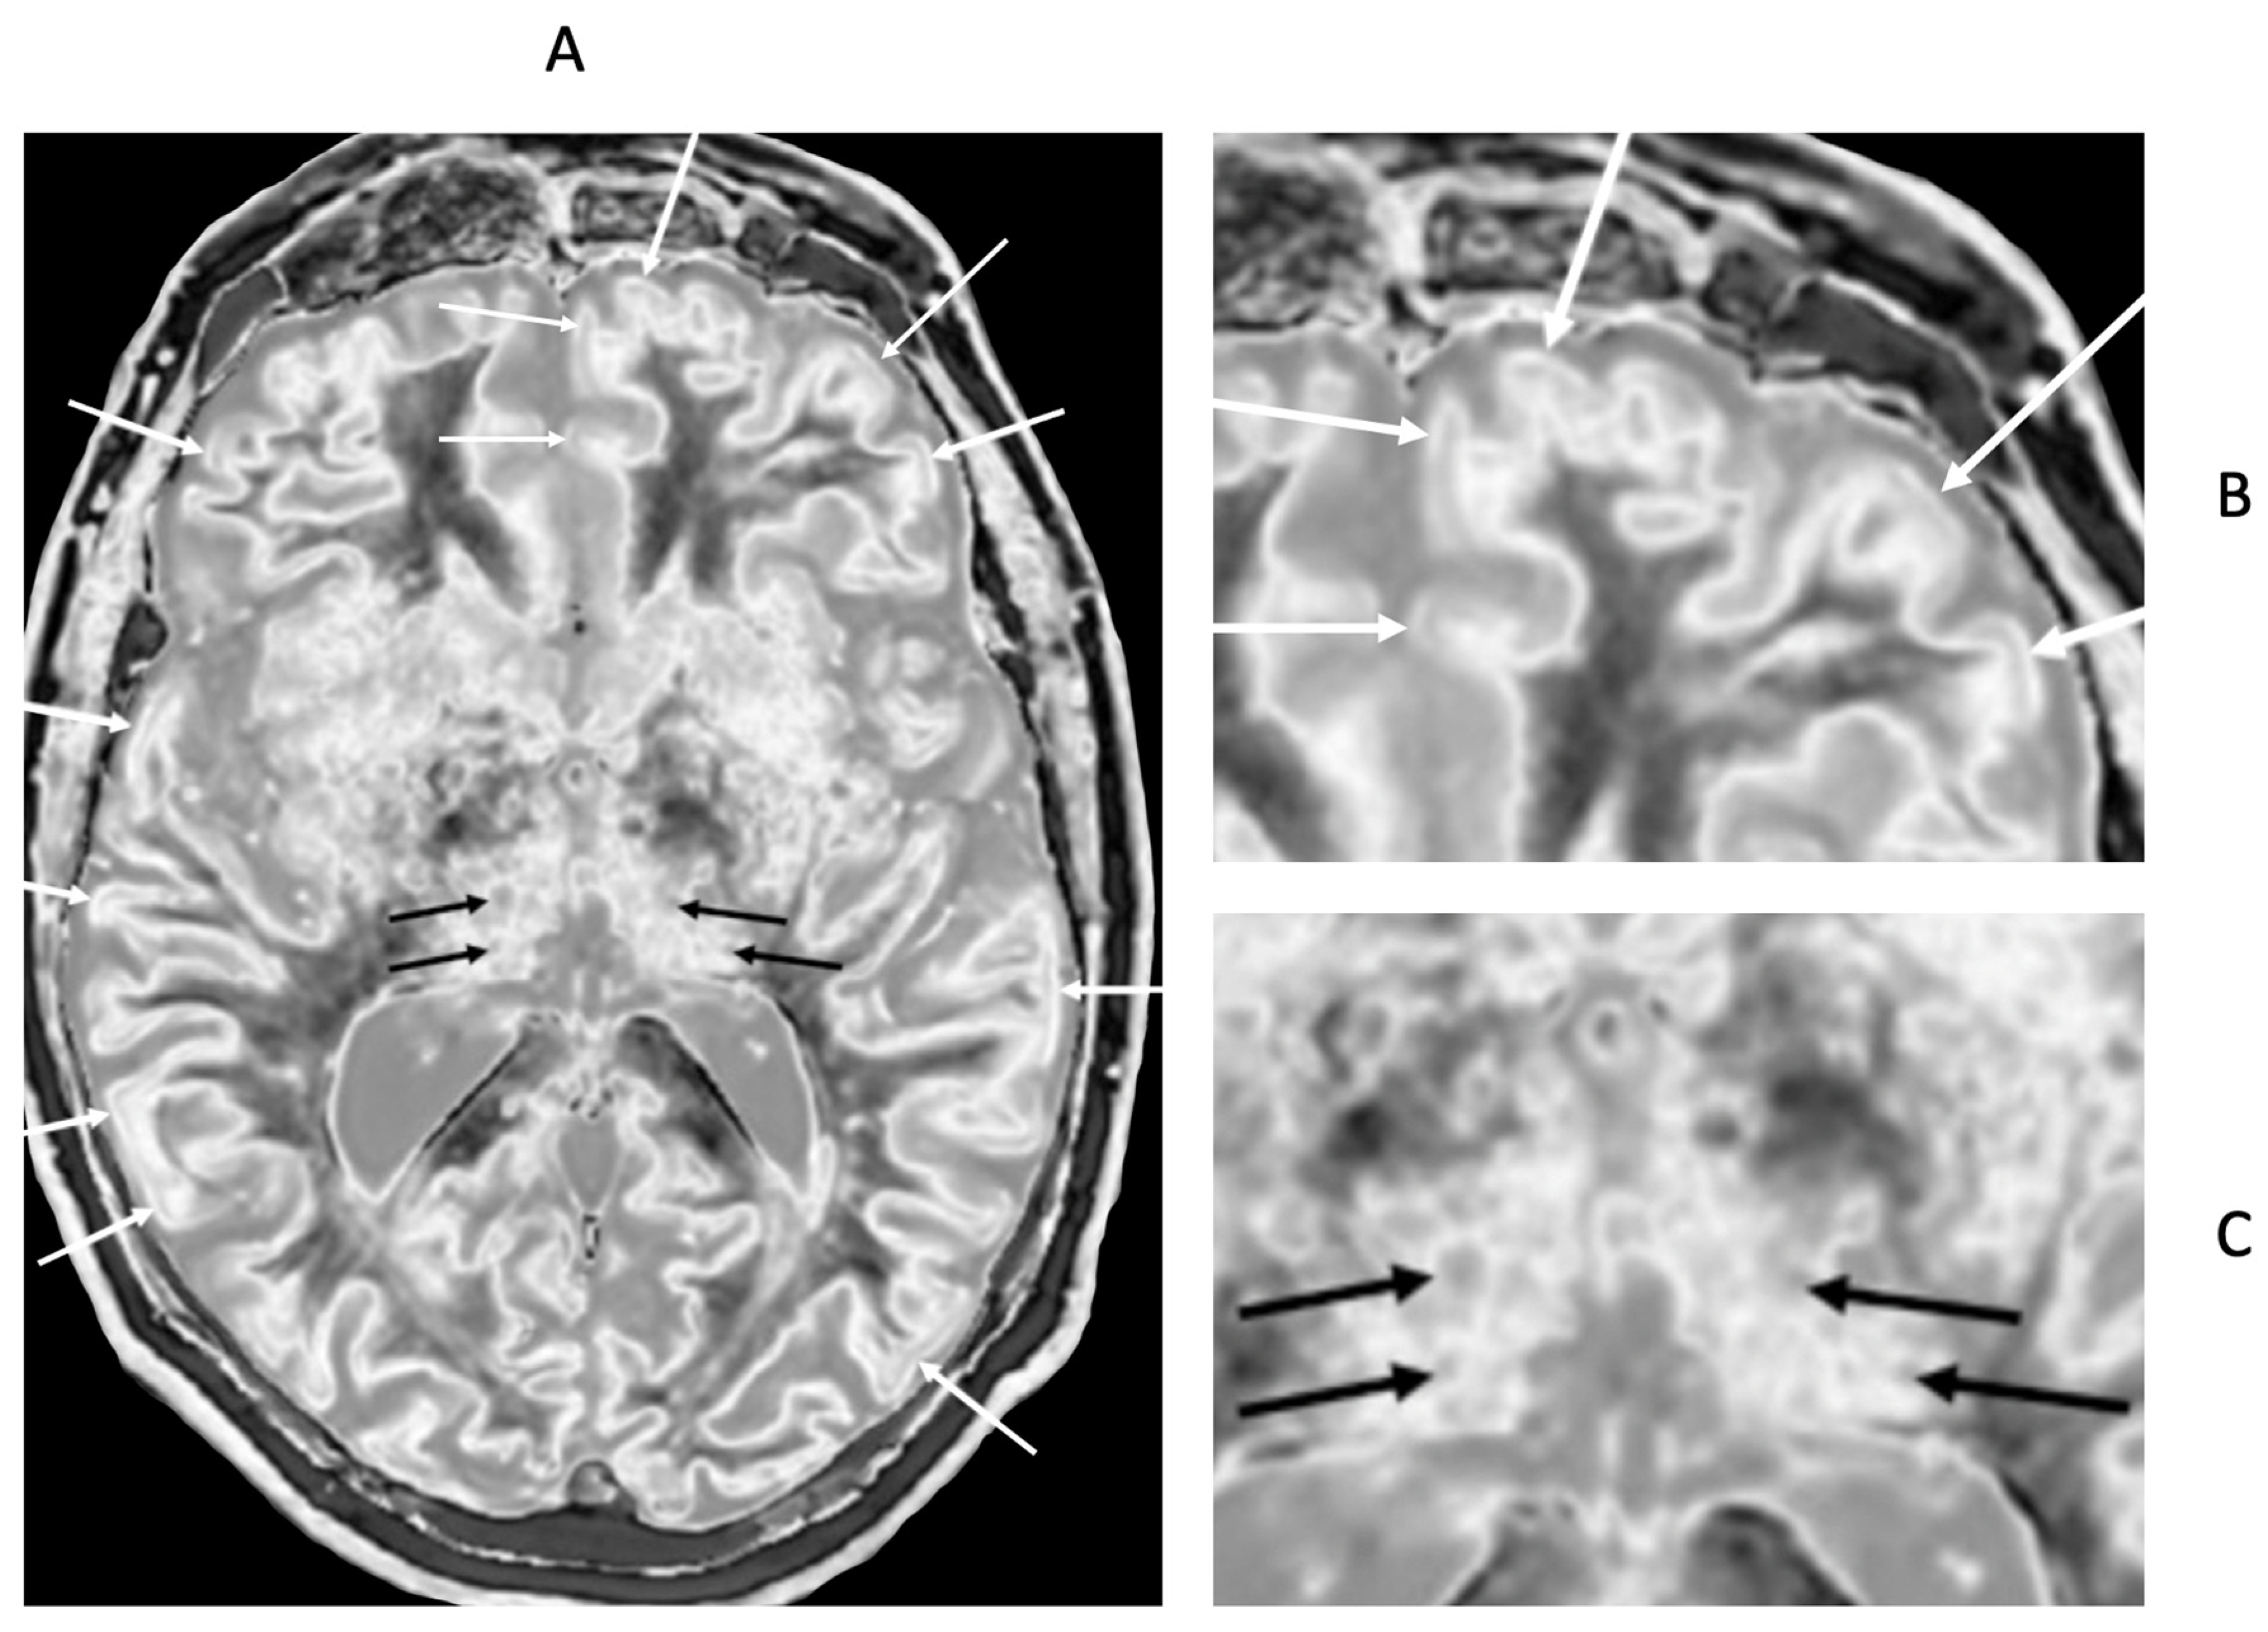

Small changes in T

1 may produce obvious abnormalities with the dSIR sequence as illustrated in a case of mild traumatic brain injury (mTBI) in an 18-year-old male patient shown in

Figure 1. No abnormality is seen on the T

2-FLAIR image in the patient (

Figure 1A). The dSIR sequence in a normal age matched control shows normal white matter in the cerebral hemispheres as low signal (dark) (arrows) in

Figure 1B. The same dSIR sequence in the patient shows abnormal high signal in his entire white matter (arrows) (

Figure 1C). High signal (light) well defined boundaries are seen between normal white and gray matter on the dSIR image in

Figure 1B. These are less obvious in

Figure 1C because of the high signal in the abnormal white matter.

Positionally matched images of the brain in a 24-year-old male patient with mTBI (A and C) and a normal control (B). (A) is a T2-FLAIR image in the patient which shows no abnormality. (B) is a narrow mD dSIR image of the brain in the normal control. The white matter in the central region of this image has a normal low signal (dark) appearance (arrows). (C) is a narrow mD dSIR image performed in the patient with the same sequence as in the control. This image shows all the patient's white matter with abnormal high signal (light) (arrows) rather than the normal low signal (dark) appearance in the control (arrows) (B). There is a night and day difference in signal between normal and abnormal white matter in (B) and (C). High signal boundaries are seen between normal white matter and normal gray matter in (B). These are less obvious in (C) because of the high signal in the abnormal white matter.